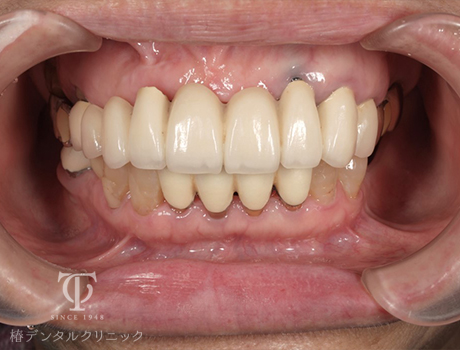

正面観AGCテレスコープ義歯装着

- 症状

- 右上の痛み

- 治療期間

- 約1年半

- 治療費用

- (上顎)インプラント治療:473,000円×2

(上顎)AGCテレスコープ義歯:1,500,000円

(下顎)インプラント治療:473,000円×2

右上の歯が痛いということで来院されました。インプラントとAGCテレスコープという方法でかみ合わせを再構築しました。

【リスク・副作用】

インプラント治療後、痛みや違和感、出血、腫れなどが出る事があります。喫煙者、糖尿病などの方の場合、歯が生着しない場合があります。入れ歯を清潔に保たないと虫歯や歯肉炎、歯周病になるリスクがあります。